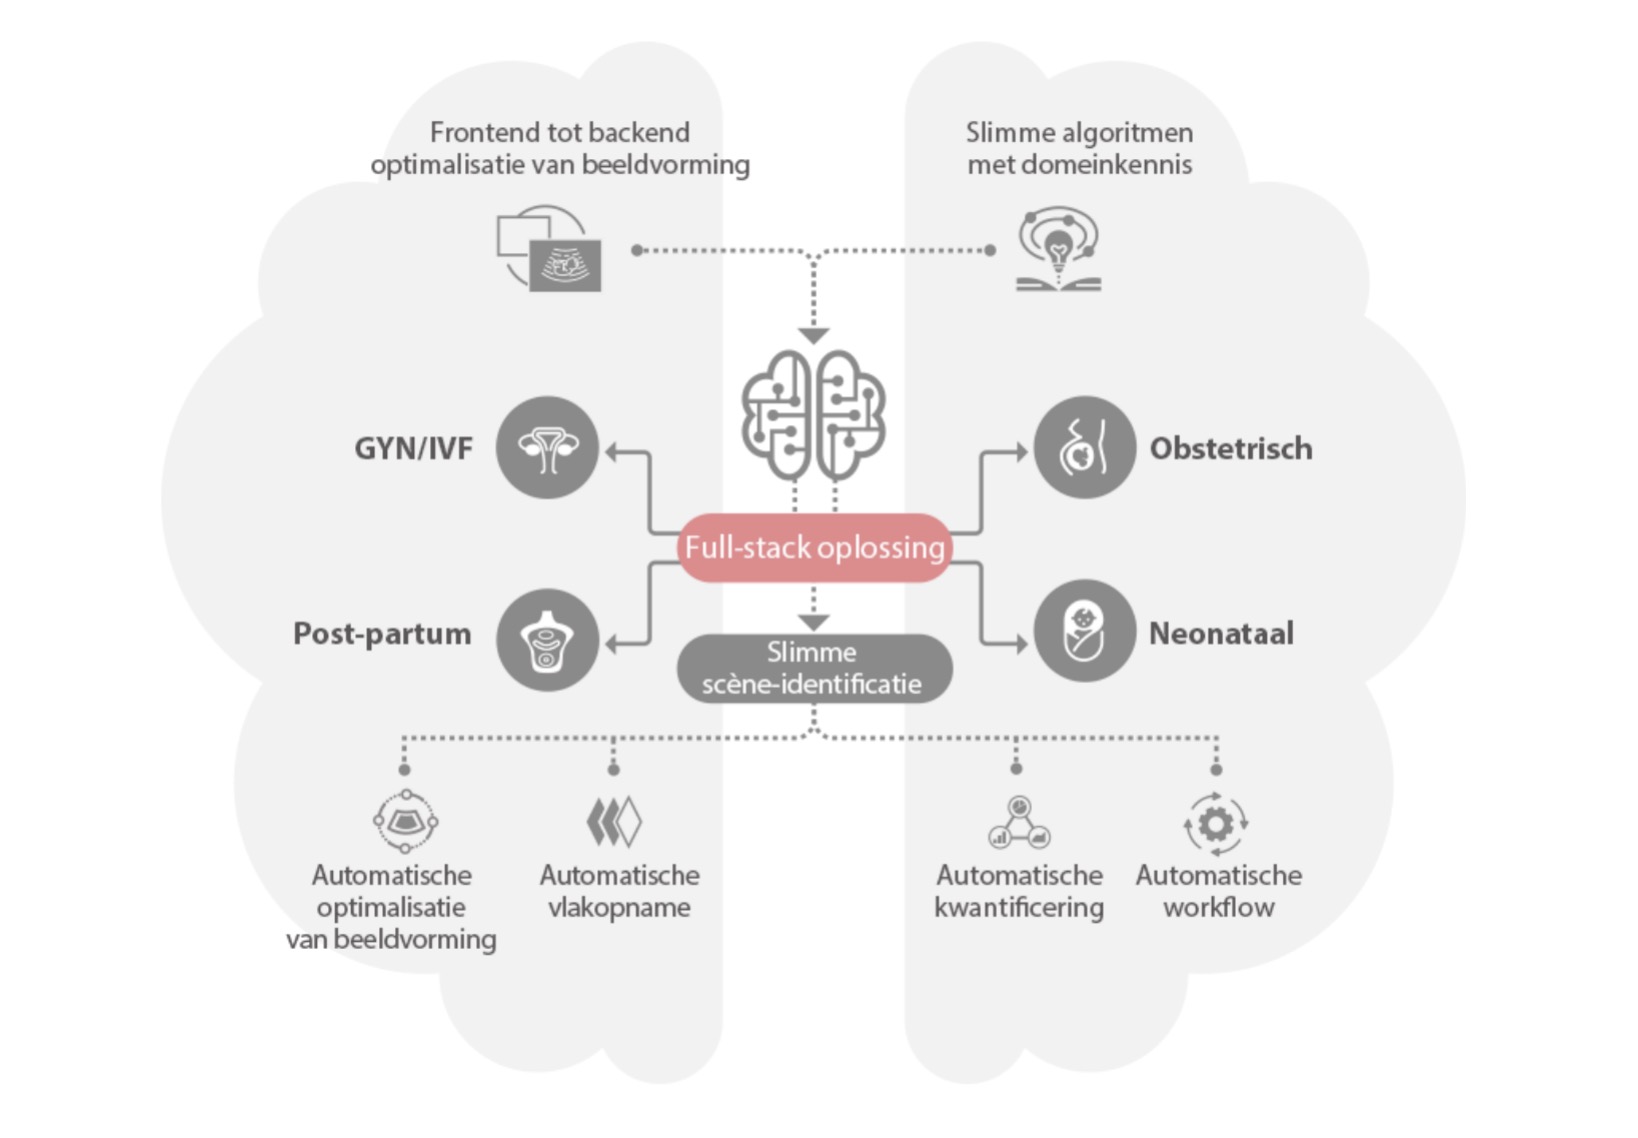

Full-stack oplossing aangedreven door ZST+

Het ZST+ platform is een buitengewone innovatie en revolutie in de wereld van ultrasound. Het transformeert ultrasoundgegevens van conventionele bundelvorming naar kanaalgegevensverwerking. Het overwint de traditionele afweging tussen ruimtelijke resolutie, temporele resolutie en weefseluniformiteit, en levert een uitzonderlijke beeldkwaliteit voor oneindige beeldvormingsoplossingen met non-stop verbeteringen.